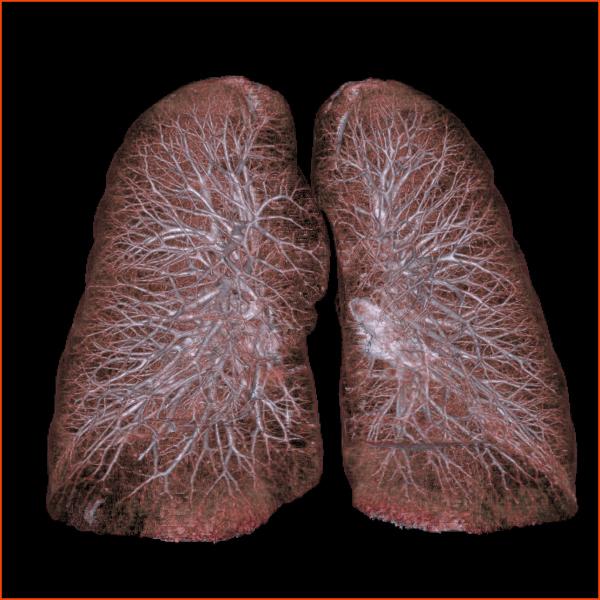

DePuy Synthes Spine announced it is expanding its collaboration with Brainlab through the worldwide launch of navigation-ready instrumentation for its spine systems and an exclusive global agreement to co-market Airo Mobile Intraoperative CT (computed tomography) by Brainlab.